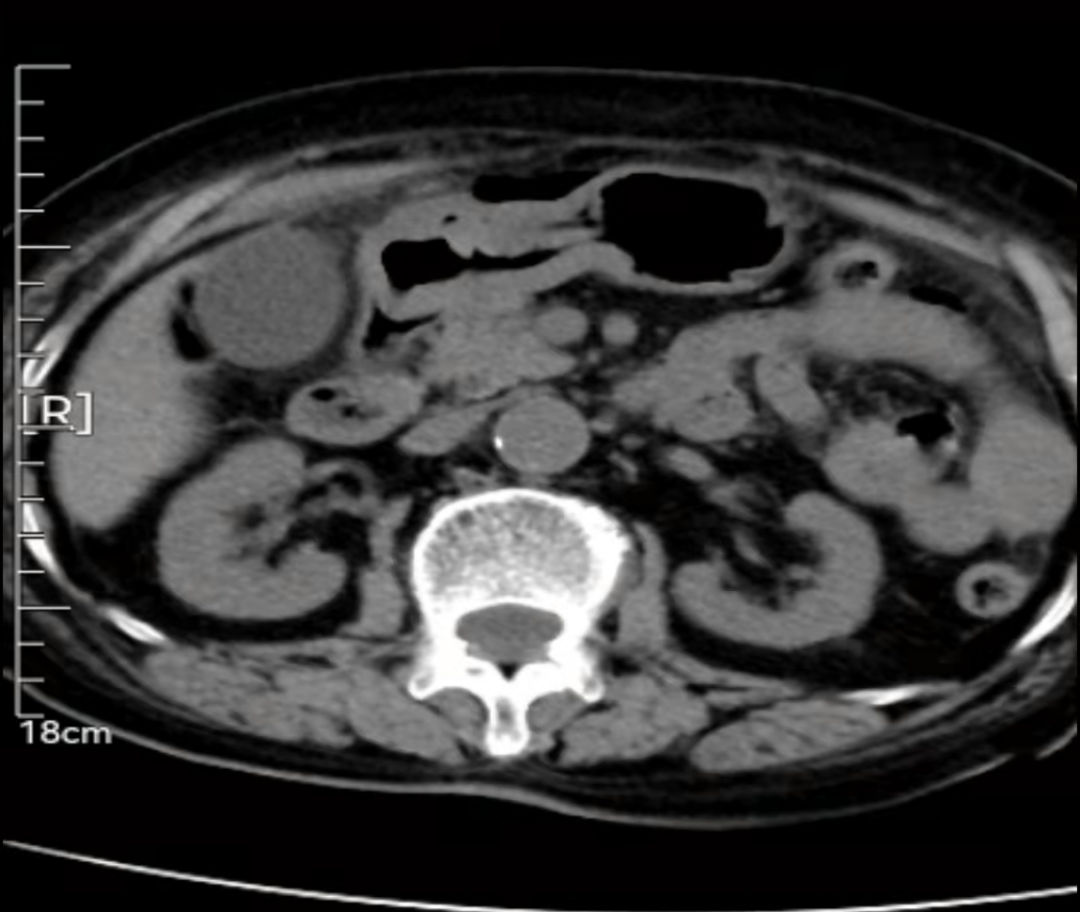

时下正值全国各地新冠疫情防控攻坚阶段,南京市溧水区人民医院普外科借助多学科联合诊疗优势,抗疫、诊疗两不误,成功救治一例高龄消化道穿孔患者。 患者许大妈,84岁高龄,因“间断上腹部疼痛2月,加重1天”于晚21点来我院急诊就诊。患者年龄大、基础疾病多、腹痛明显、心率增快、血压偏低,病情危重,CT提示“消化道穿孔伴弥漫性腹膜炎”。消化道穿孔进展迅速,不及时治疗可能会出现弥散性腹膜炎甚至感染性休克,危及生命。普外科主任张恒及值班医生立即对病人及家属开展流行病学调查,迅速完成核酸采样,同时开启绿色通道收入缓冲病房,救治病人。 老年患者出现消化道穿孔,需要考虑胃部恶性肿瘤导致穿孔的可能性。患者高龄,基础疾病多,病情危重,“保守还是手术?”,“开腹手术还是腹腔镜手术?”,“穿孔修补术还是胃部分切除术?”……嵇振岭院长听取汇报后,连夜赶到医院组织安排影像科、消化科、内镜中心、病理科、麻醉科及ICU等科室组成多学科MDT诊疗团队,对患者的病情及治疗方案进行讨论并与家属进行了深入沟通,决定行“腹腔镜+胃镜”双镜联合手术。 深夜,嵇院长带领各科室为患者进行手术,行腹腔镜探查,发现胃窦部前壁穿孔,内镜中心主任赵向阳行胃镜检查,联合快速病理检查排除恶性肿瘤后,在内镜下放置空肠营养管,为患者术后恢复提供营养支持通道;普外科团队同步进行腹腔镜下胃穿孔修补术+腹腔冲洗引流术…… 手术过程十分顺利,手术结束已经第二天凌晨,患者家属悬着的心也终于落了地,连声感谢医院各位专家所作的努力。术后患者经过短暂的ICU监护管理,已转回普外科病房,目前恢复良好,许大妈也露出了开心的笑容。 近年来,随着院府合作的深入发展,溧水区人民医院各种微创手术、高难度手持续开展并逐渐常规化,在诊疗手段方面也不再是单科室“单打独斗”,而是走多学科讨论协作制定个体化治疗方案路线,各种新思路、新方法如雨后春笋般涌出,为合理诊断、科学治疗提供了更坚强有力的保障。 疫情之下,溧医人始终秉承“新冠防控与医疗救治并重,两手都要抓,双拳都要硬”的要求,一手坚持疫情防控工作不放松,一手抓好开展急救医疗工作,为维护溧水及周边地区的健康卫生工作付出最大的努力。 健康所系,性命相托,溧医人用行动诠释医务工作者的初心,一如既往,竭尽全力救治患者,为患者生命保驾护航! |